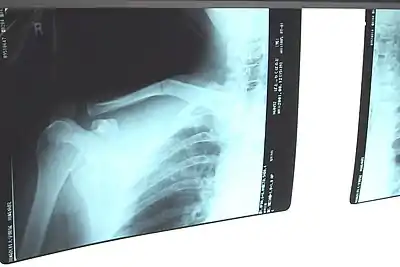

Fracture de la clavicule

Il est radiographique affirmé par la radiographie de face. Idéalement il s'agit d'un cliché « clavicule de face » ascendant à 30° sur l'horizontale qui visualise mieux l'os et le foyer. Le fragment proximal est habituellement déplacé vers le haut en raison de la traction du muscle sterno-cléido-mastoïdien, le fragment distal étant attiré vers le bas par le poids de l'épaule et la traction du muscle deltoïde. Il se produit un raccourcissement par perte de l'arc boutant claviculaire avec un déplacement du moignon de l'épaule vers la ligne médiane.